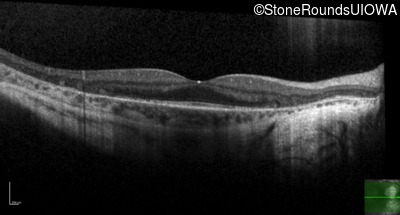

Age at visit: 34 years